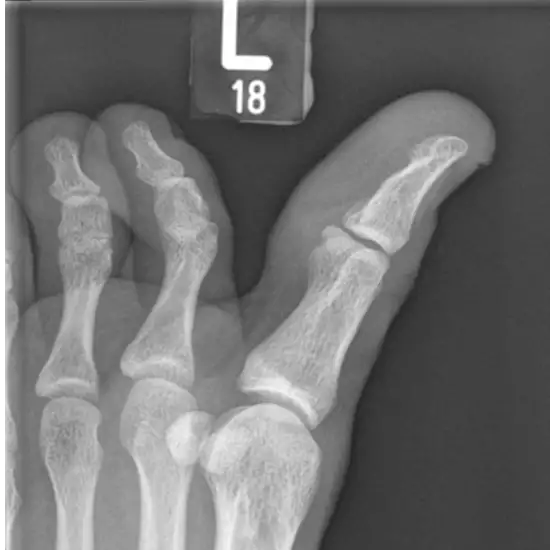

An X-ray of the big toe joint is a safe and painless test that uses a little amount of radiation to visualize the bones of the great toe and the surrounding soft tissues (skin and muscles).

• To diagnose any broken or fractured big toe bones and track the broken bone's healing after it has been set.

• To rule out any possible infection, osteoporosis, deformities or irregular bone growth, and arthritis (inflammation of the joints).